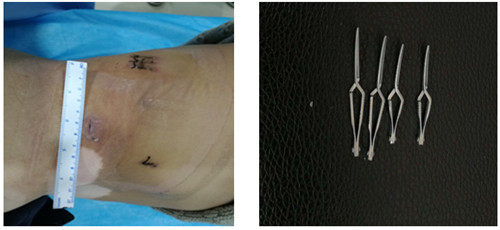

后腹腔镜技术,即俗称的“打眼”,于腰部不同部位作3个5-12毫米的小切口,通过这些切口插入摄像镜头及手术器械,通过摄像镜头将各个组织、脏器传输到电视屏幕上,外科医生通过观察图像用各种手术器械在腰部进行操作来完成手术。

如图一图二为肿瘤位置及大小,图三即为手术操作通道(5mm、10mm、12mm),术中游离出肾动脉后,用图四的血管夹临时阻断肾脏血液供应,剜除肿瘤后,在腔镜下缝合肾脏,确定缝合严密,再恢复肾脏血供!要求阻断时间不能超过30分钟,此例患者阻断17分钟!此类手术技术难度大,腹腔镜下缝合要求高,并对血供阻断有时间要求!